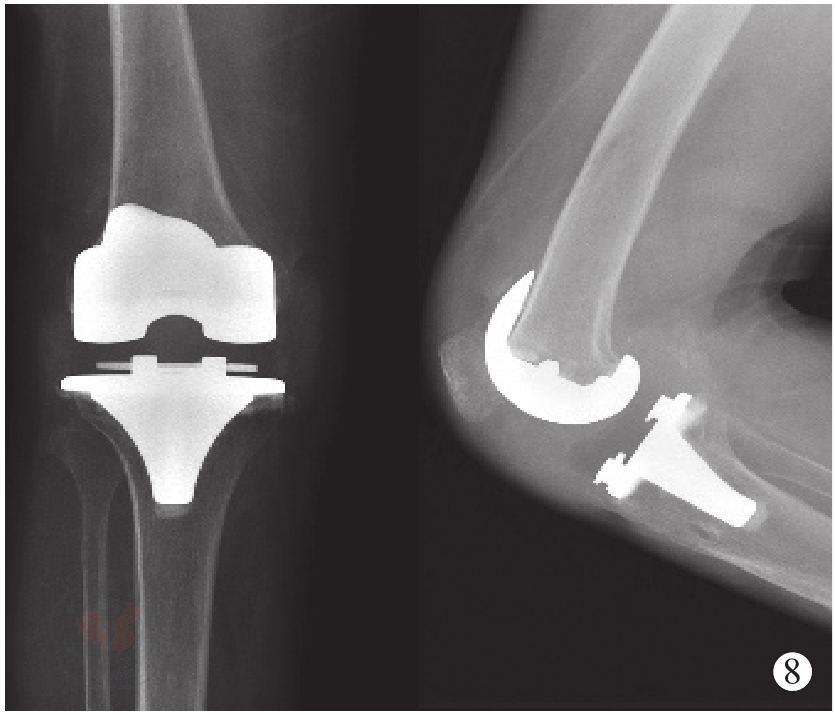

图8 术后12个月右膝正侧位X线,示假体无异常